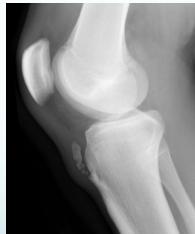

X-rays

- Which bone, and which site in bone?

- Solitary or multiple?

- Bone forming or bone eating?

- Margins: well-defined or ill-defined?

- Calcifications in the lesion?

- Is cortex eroded or destroyed?

- Is there periosteal new bone formation?

- Soft tissue extension?